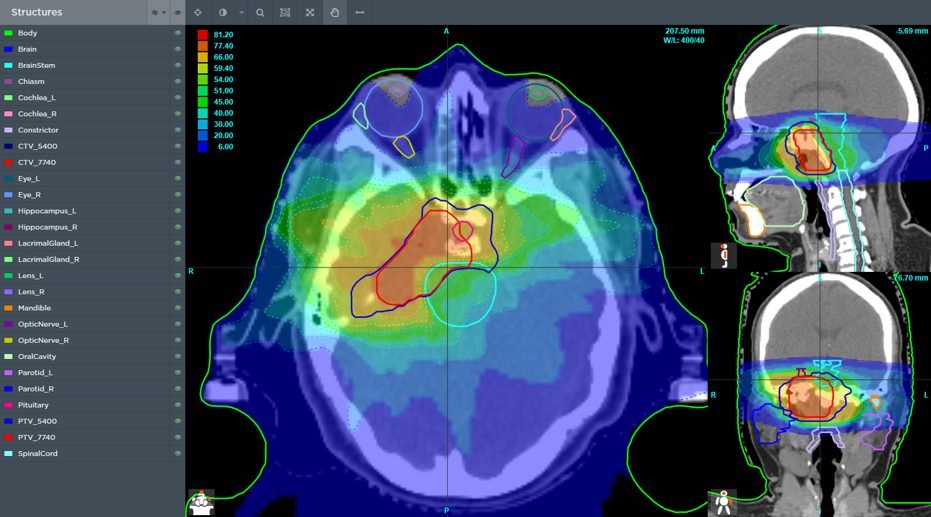

Súťaže s oficiálnym názvom 2020 American Association of Medical Dosimetrists Plan Study sa zúčastnilo 325 súťažiacich z celého sveta. ,,Predmetom súťaže bolo vytvoriť čo najlepší ožarovací plán pre daného fiktívneho pacienta. Podkladom bolo jeho CT so zakreslenými rizikovými orgánmi a nádorom, ktorý chceme ožiariť,“ objasňuje fyzik Dalibor Lojko, ktorý má v tejto oblasti prax 12 rokov. Súťaž sa realizuje každý rok, vždy sa vyberie nejaká, zväčša zriedkavá diagnóza, ktorá sa potom prezentuje a diskutuje na viacerých mítingoch. Tento rok sa riešila diagnóza chordóm. Ide o zriedkavý druh rakoviny, ktorý rastie v kostiach lebky a chrbtice. Keďže sa zväčša nachádzajú v blízkosti miechy a mozgu je potrebné ich liečiť veľmi opatrne. Pri súťaži boli dané rôzne podmienky, ktoré mal návrh ožarovacieho plánu spĺňať a 22 bodovo hodnotených kritérií.